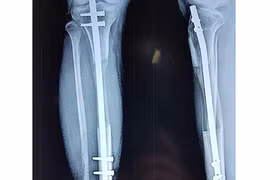

(Khoahocdoisong.vn) - Kéo dài và thu ngắn chân là các loại hình phẫu thuật nhằm điều trị cho những người bị tật chân cao, chân thấp do di chứng thương tật, do tai nạn lao động, những trường hợp bị viêm xương, bị bệnh bại liệt hoặc do phải cắt u xương…

Nam thanh niên 28 tuổi ở Cà Mau bị sốt bại liệt lúc nhỏ để lại di chứng chân phải ngắn hơn chân trái 4,2 cm, mới đây, anh quyết định thực hiện ca phẫu thuật kéo dài xương chân để đi lại thăng bằng.